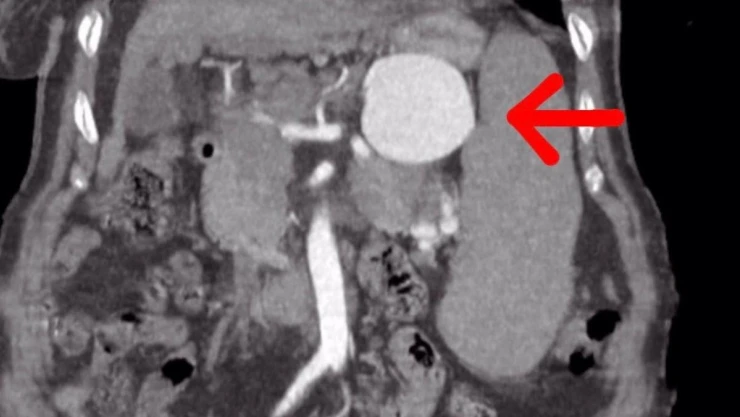

Yapılan ameliyat ile ilgili gazetecilere açıklamalarda bulunan Op. Dr. Volkan Burak Taban, hastanın gastroenteroloji kliniğinden kendilerine geldiğini, dalak arterinde ciddi bir anerizma şüphesinden bahsedildiğini söyledi. Değerlendirmeler sonrası ilaç tetkikleri istediklerini belirten Dr. Taban, "Yapılan tomografide teyzemizde dalak arterinde oldukça geniş dev diyebileceğimiz anerizmanın yani baloncuklaşmanın olduğunu gördük. Normalde dalak anerizması diyebilmemiz için baloncuklaşma diyebilmemiz için 20 milim yani 2 santimin üstüne çıkması lazım. Ama gördüğümüzde bizde şaşırdık. Çünkü yaklaşık 7 santimi geçen bir dalak anerizması vardı. Hastanın bu anerizmanın içerisinde tamamen kan dolduğu için her an patlama riski vardı. Allah korusun hastanın hayatını kaybetme riski ile de karşı karşıyaydık. Hasta ile ilgili hemen multidisipliner olarak bir değerlendirme yaptık. Hem gastroenteroloji, hem genel cerrahiden Serhat hocamız, hem radyoloji kliniğimiz ile beraber değerlendirme yaptık. Hastamızın 15 yıldır mücadele verdiği bir karaciğer sirozu da bizim kararlarımızda etkili oldu” dedi.